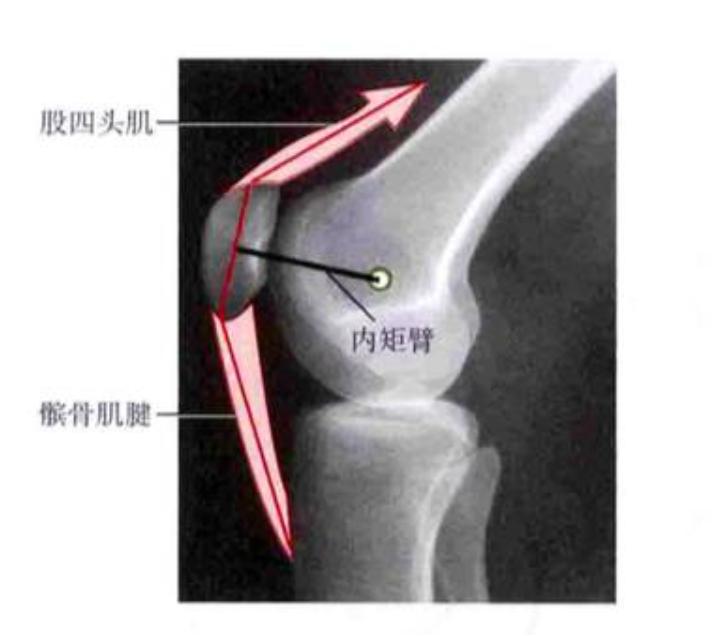

髌骨由股四头肌和髌骨韧带,一上一下连接,通过肌肉的拉动,在膝关节屈曲和伸直的过程中起重要作用。而髌骨则在股骨内外髁凹槽之间滑动。髌骨作为支点,在保护膝关节的同时,增加了肌力距(类似杠杆的作用),使得膝关节的运动效率更高。